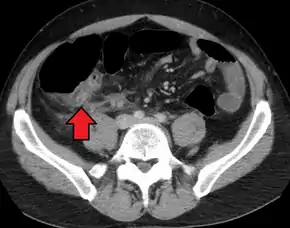

A CT scan demonstrating acute appendicitis (note the appendix has a diameter of 17.1 mm and there is surrounding fat stranding)

A fecalith marked by the arrow that has resulted in acute appendicitis.

Where it is readily available, computed tomography (CT) has become frequently used, especially in people whose diagnosis is not obvious on history and physical examination. Although some concerns about interpretation are identified, a 2019 Cochrane review found that sensitivity and specificity of CT for the diagnosis of acute appendicitis in adults was high.[49] Concerns about radiation tend to limit use of CT in pregnant women and children, especially with the increasingly widespread usage of MRI.[50][51]

The accurate diagnosis of appendicitis is multi-tiered, with the size of the appendix having the strongest positive predictive value, while indirect features can either increase or decrease sensitivity and specificity. A size of over 6 mm is both 95% sensitive and specific for appendicitis.[52]

However, because the appendix can be filled with fecal material, causing intraluminal distention, this criterion has shown limited utility in more recent meta-analyses.[53] This is as opposed to ultrasound, in which the wall of the appendix can be more easily distinguished from intraluminal feces. In such scenarios, ancillary features such as increased wall enhancement as compared to adjacent bowel and inflammation of the surrounding fat, or fat stranding, can be supportive of the diagnosis. However, their absence does not preclude it. In severe cases with perforation, an adjacent phlegmon or abscess can be seen. Dense fluid layering in the pelvis can also result, related to either pus or enteric spillage. When patients are thin or younger, the relative absence of fat can make the appendix and surrounding fat stranding difficult to see.[53]